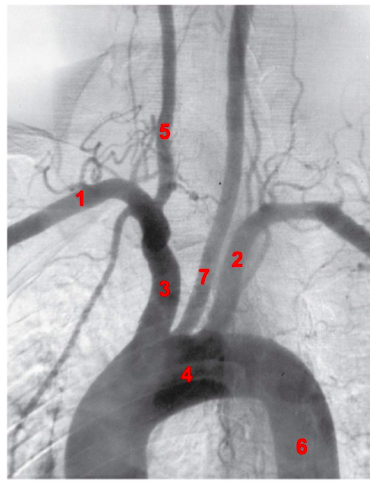

label 1-7

1: right subclavian artery

2: left subclavian artery

3: brachiocephalic trunk

4: aortic arch

5: right common carotid artery

6: descending aorta

7 left common carotid artery